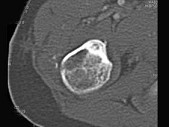

- 单项选择题男,28岁, 右上肢疼痛,夜间加重, 服用止痛药可缓解,结合图像, 最可能的诊断是 ( )

C、骨样骨瘤